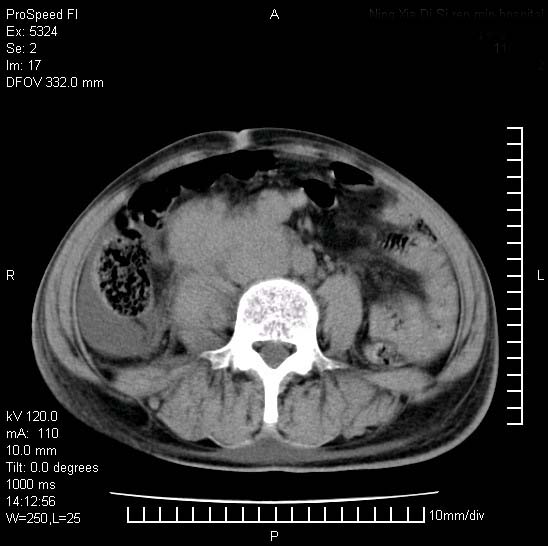

患者阴囊肿大14月,腰痛2个月,咳嗽,咳痰1周,患者现在肾功异常,做增强有些担心,我们用的是欧乃派克.

右侧肾癌伴腹膜后淋巴结转移!

右侧肾癌后腹膜转移,腹腔少量积液

腹膜后淋巴结肿大包饶腔静脉,双肾病变,建议增强

双肾均有软组织密度舯物,腹膜后淋巴结肿大包饶腔静脉------考虑为恶性占位病变,转移瘤可能。

左肾也有问题呀///

支持:双肾均见软组织密度肿块影,腹膜后淋巴结肿大包绕腔静脉------考虑为恶性占位病变,转移瘤可能。

1)考虑双肾恶性肿瘤(肾癌?)。2)腹膜后淋巴结肿大,多为肿瘤转移所致。

腹腔积液,双肾均有稍高密度肿块,主动脉旁广泛淋巴结肿大,融合,无显著肿块坏死征像,多考虑淋巴瘤累及双肾,不排除肾癌伴转移(肾癌这么大应该较多坏死了),另阴囊肿大,不知是实质肿大还是阴囊积液,如是是积液,多为腹腔肿块压近睾丸静脉所致,如是是实性的,多为淋巴瘤

1、淋巴瘤,双肾转移瘤;2、双侧肾癌,伴有腹膜后淋巴结转移。

双肾周围及腹膜后改变符合恶性病变,现在关键是要明确阴囊肿大的原因,是否为肿瘤性病变.如阴囊为恶性肿瘤那一切用转移即可解释,如阴囊为水肿改变,那需重新分析检查明确.

双肾均有软组织肿块伴腹膜后淋巴结肿大融合,右侧结肠旁沟积液;考虑恶性肿瘤。转移瘤?淋巴瘤?

阴囊肿大是实质性的么,为什么不扫阴囊,此扫描做的是什么部位,肾脏没包括全,也可以考虑生殖系统肿瘤转移

双肾增大,腹膜后多发肿大淋巴结影.首先考虑淋巴瘤.

双肾增大,结合腹膜后淋巴结肿大,考虑双肾恶性肿瘤并转移可能。

双肾癌并腹膜后淋巴结转移

考虑恶性淋巴瘤侵及双肾,腹膜后淋巴结肿大。